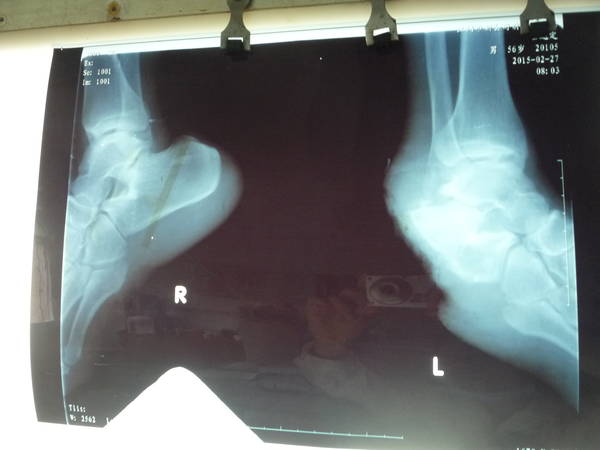

[组织瓣] 跟骨结节缺损并足底皮肤缺损